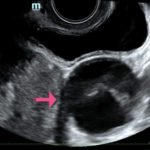

The ultrasound video clip demonstrates a transverse view of the pelvis using the endocavitary probe. The bladder can be seen on the anterior portion of the scan (yellow arrow), while the uterus with an intrauterine pregnancy is visible posteriorly (blue arrow). The thickened appearance of the uterine wall is also indicative of pregnancy. A large, anechoic cystic structure measuring approximately 5 cm is seen in the vicinity of the patient’s left adnexa (pink arrow), which raises concerns for ovarian torsion.1

Based on the clinical presentation and the bedside ultrasound, obstetrician-gynecologist (OB/gyn) was emergently consulted and the patient was transferred to the operating room (OR) where she was found to have a paratubal cyst in the left fallopian tube with associated isolated tubal torsion. After manually de-torsing the tube, which was initially dilated and dusky, blood flow was restored and the color returned to normal. A cystectomy was performed without complications. The patient was discharged later that day after the follow-up ultrasound showed reassuring fetal heart tones and good blood flow to the left ovary.

When using bedside ultrasound, the most reliable indicator of ovarian torsion is an enlarged ovary, greater than 4 cm in size.3In addition to looking for an enlarged ovary, additional sonographic findings that can be indicative of torsion include a solid, cystic, or complex mass, with or without fluid, or cystic hemorrhage.4 Ovarian cysts are risk factors due to their capacity to serve as pivot points for ovaries to twist around.1,4 When performing the ultrasound, it is possible to see little or no intra-ovarian venous flow or absent arterial flow, but because there is dual blood supply to the ovaries from the ovarian and uterine arteries, normal vascularity does not exclude torsion.